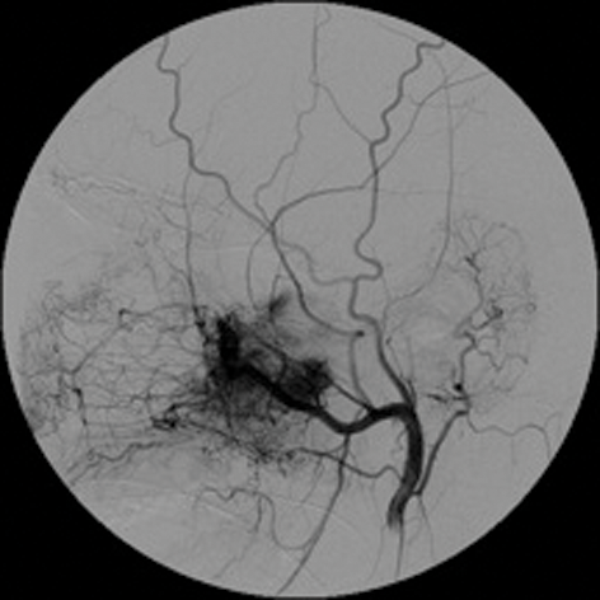

Preoperative embolisation is most commonly used in the management of juvenile nasal angiofibroma (JNA) which is an uncommon benign tumour of adolescent males with a very rich blood supply. This lesion arises in the pterygo-palatine fossa and then expands aggressively into the nasopharynx and nasal cavity through the sphenopalatine foramen.

Embolisation is very effective in minimising intraoperative blood loss and is now a well-accepted part of the treatment of JNA [2]. (Figure 1 shows a case of preoperative embolisation of a juvenile angiofibroma).

Figure 1: Juvenile angiofibroma before and after embolisation.